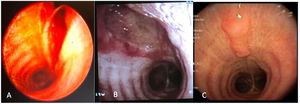

The cryobiopsy was performed under general anesthesia with placement of an endotracheal tube (ETT). After the procedure, residual but persistent bleeding was identified, and bronchofibroscopy revealed a 3cm longitudinal tear in the posterior wall of the trachea, up to the submucosa (Fig. 1A).

The patient was admitted to the Intensive Care for clinical and imaging surveillance, with no evidence of pneumomediastinum, pneumothorax or subcutaneous emphysema. Conservative therapy was chosen (monitoring). Endoscopic reassessment after 4 days showed a laceration on the posterior wall of the trachea with signs of flap healing (Fig. 1B). The injury was classified as grade I according to Cardillo et al.1 She was discharged after 4 days, with indication for monitoring. Endoscopic reassessment after 1 month showed complete healing of the tear, without interruption of continuity (Fig. 1C).